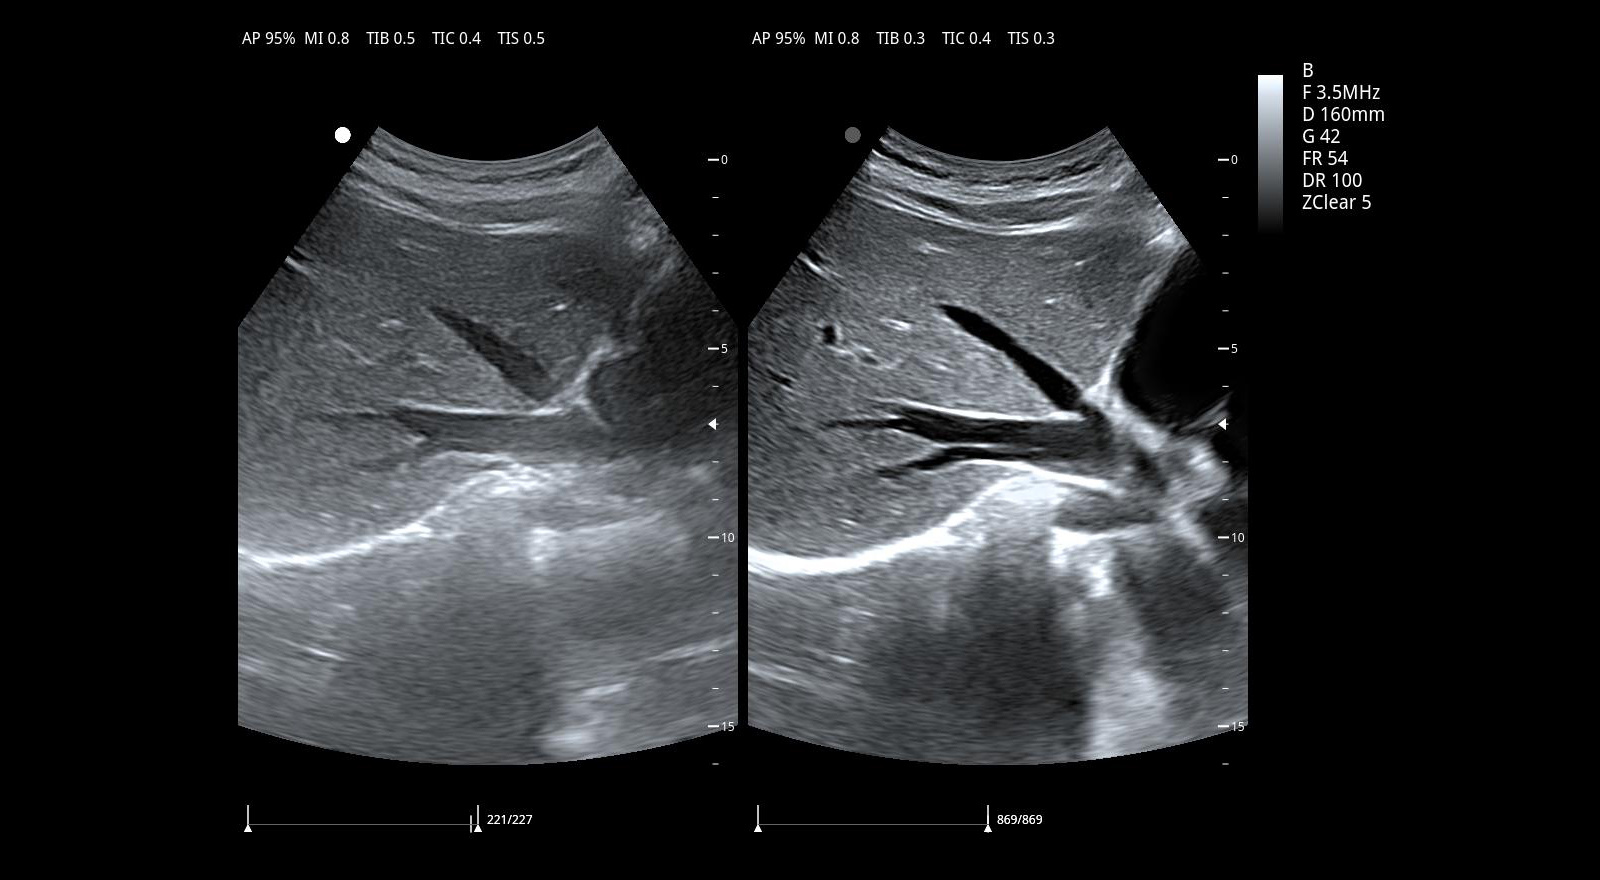

Imágenes clínicas extraordinarias